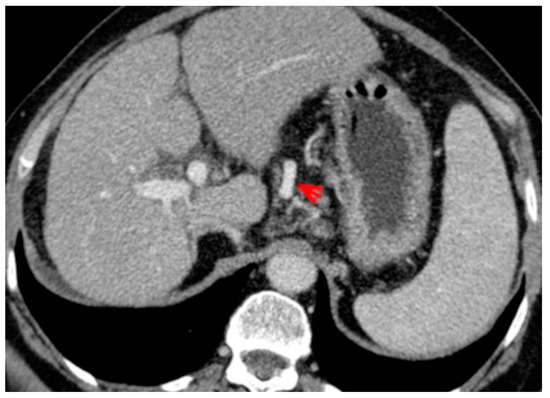

For this study, the images were retrospectively analyzed in consensus by two readers with experience in the field of abdominal imaging. The two readers assessed the following CT features: (1) The presence or absence of paraoesophageal varices and the size(mm) of the largest varix (Figure 1); (2) the presence or absence of paragastric varices and the size (mm) of the largest varix (Figure 2); (3) the largest diameter of the left gastric vein (Figure 3); (4) the presence or absence of splenorenal shunts and the size(mm) of the shunt (Figure 4); (5) the presence or absence of a repermeabilized round ligament and the size(mm) of it (Figure 5).

Figure 1. Axial contrast-enhanced CT shows enlarged paraoesophageal varices (red arrow).